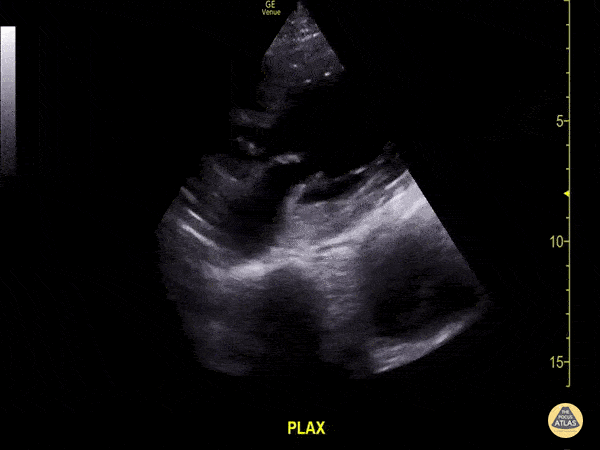

Don’t be distracted by the abnormal cardiac function in this clip…notice deep to the pericardium a thoracic aorta aneurysm is seen with moderate amount of intramural thrombus. Image courtesy of Aventura Ultrasound; Their original Twitter posting can be found here.